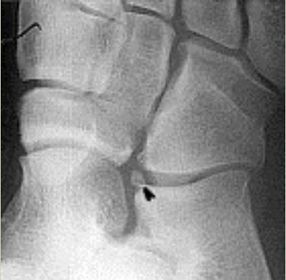

| What is this? | Os calcaneus secundarius |

| What is this? | Os supracalcaneum |